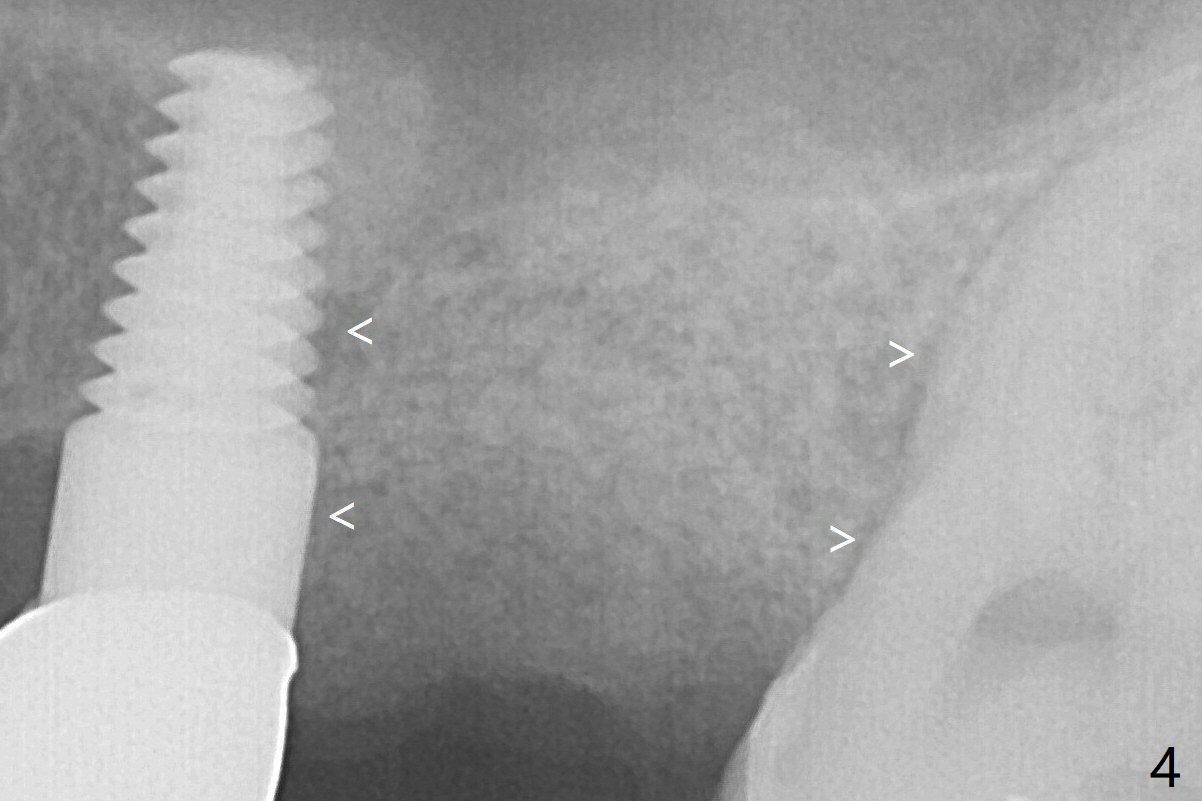

By breaking the proximal contacts, the crown, abutment and implant at #14 are shaken loose using forceps.  Finally the crown breaks off.  Make a slot on the top of the abutment and use a screw bit to turn the abutment/implant counterclockwise.  There is abundant granulation tissue with arterial hemorrhage associated with removal.  The defect involves the distal surface of the implant at #13 and the mesial surface of the tooth #15.  Therefore bone graft is deposited in these surfaces (Fig.4 arrowheads).  The bone height 5.5 months postop should be enough for implantation (Fig.6).